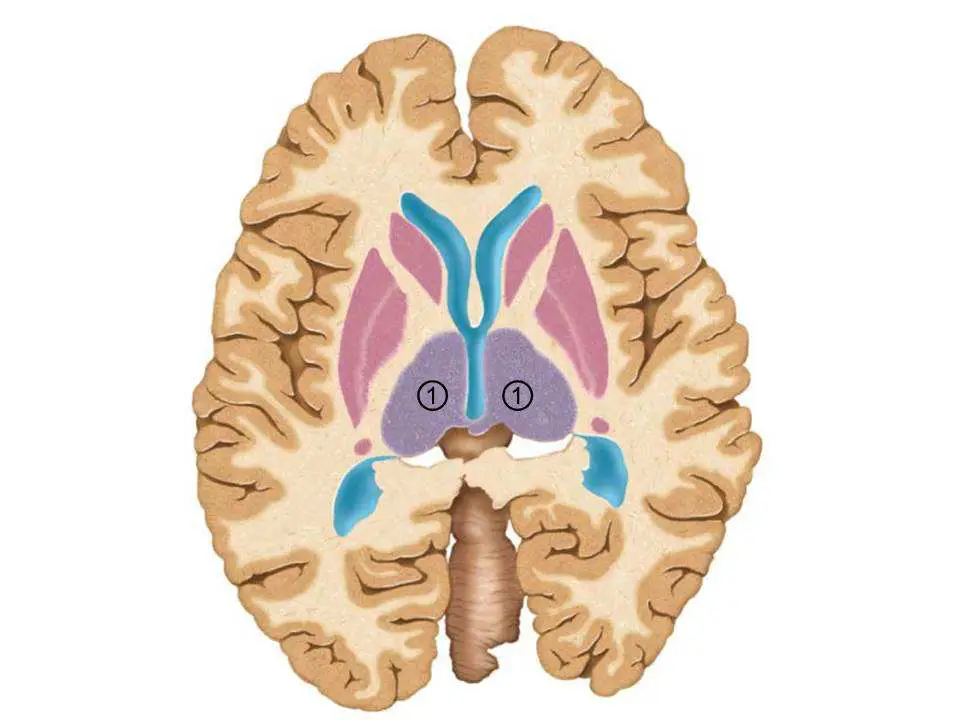

下圖為腦的水平切面,其中標示為 ①的構造是:

圖片為腦部水平切面(下視圖),可清楚辨識以下結構:

- 藍色(中央):側腦室(lateral ventricles)的體部及第三腦室(third ventricle),呈 Y 字形或蝴蝶形延伸。

- 粉紅色(雙側大型卵圓形結構,標示 ①):位於第三腦室兩側的大型卵圓形灰質結構,即丘腦(thalamus)。丘腦在此切面緊鄰第三腦室兩側,向外以內囊後腳(posterior limb of internal capsule)與豆狀核分隔。

- 藍色(外側):側腦室顳角(temporal horns of lateral ventricles)。

- 中央深色區域:第三腦室及下丘腦(hypothalamus)區域。

標示 ① 的結構(粉紅色、雙側對稱的卵圓形大型灰質核團)緊鄰第三腦室兩側,符合**丘腦(thalamus)**的標準軸位切面位置特徵。在此層面,尾狀核已不明顯(其頭部位於更前上方),豆狀核(殼核+蒼白球)則位於內囊的更外側。